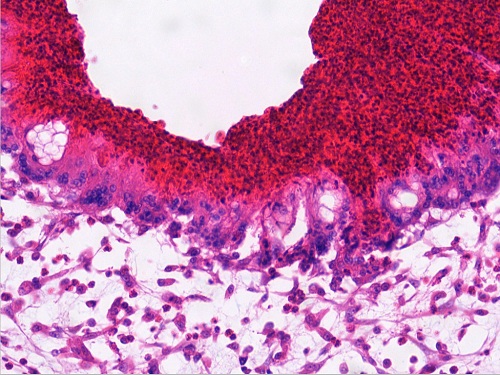

淋巴结大肠杆菌肉芽肿1